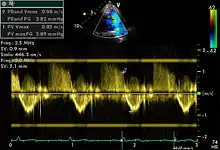

Spectral doppler

Spectral doppler through pulmonary vein

Spectral doppler is presented similarly to M-mode in which the doppler information is plotted as a spectrogram. This can be both "continuous" and "pulse" wave where the former shows the spectrum along a specific line and the latter shows within a small window along that line. Continuous wave is better at showing maximal velocities and pulse wave is better for showing flow through a small volume.

Spectral doppler is often used for quantification of flow. For example, the aortic valve area can be estimated using the continuity equation by measuring the velocity time integral (VTI) of the aortic valve & LV outflow tract; the VTI is calculated by tracing the flow on the spectral doppler curve. Spectral doppler is also useful for calculating the maximum flow and mean flow through a valve (used to grade valve stenosis).